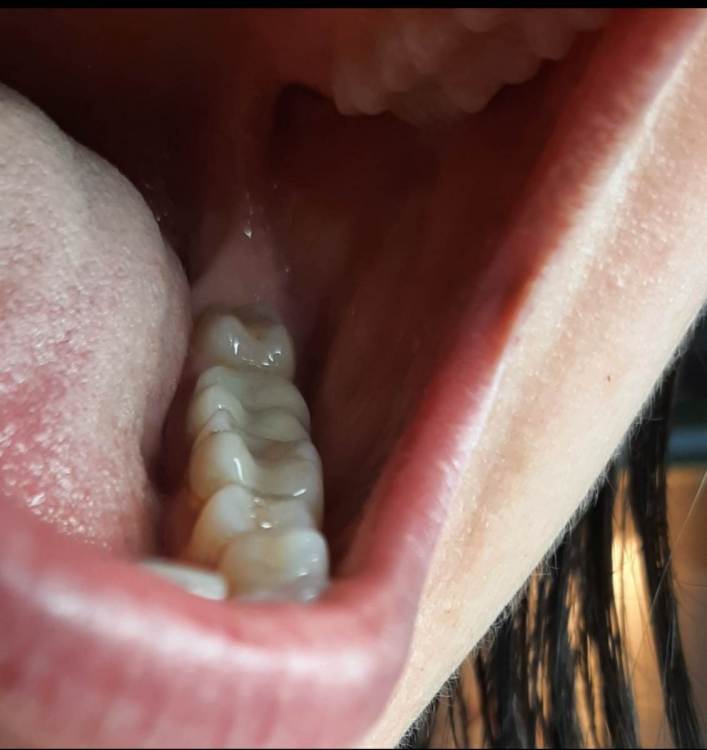

Лана-Лана Опубликовано 6 декабря, 2021 Поделиться Опубликовано 6 декабря, 2021 (изменено) Добрый день. Установили цирконевую коронку на нижнюю семёрку, при примерке я заметила что коронка низкая , но врач убедила что все впорядке типа мой зуб такой и был, самый последний бугор на контакте с восмым зубом с язычной стороны чуть ли не на уровне десны. Теперь когда жуешь и туда попадает что то твердое мясо, яблоко очень больно десну .. я сказала об этом ортопеду но она говорит что по другому не сделать, и предлагает вырвать восьмёрку и засчет этого опустится десна, но это же не выход , да и не хочу я ее удалять, раньше у меня с моим натуральным зубом таких проблем не было.... посмотрите пожалуйста снимки зуба до и фото после, действительно ли у меня был такой низкий зуб? Или это портак? На фото во рту видно что он ниже восьмёрки а край с язычной стороны ещё ниже...и если это плохо сделанно? Можно ли просить переделки ведь он ещё на гарантии? Или это проблемно снять? И что вообще в таких случаях делать если ортопед отказывает в переделке? Писать претензию? Изменено 6 декабря, 2021 пользователем Лана-Лана Ссылка на комментарий